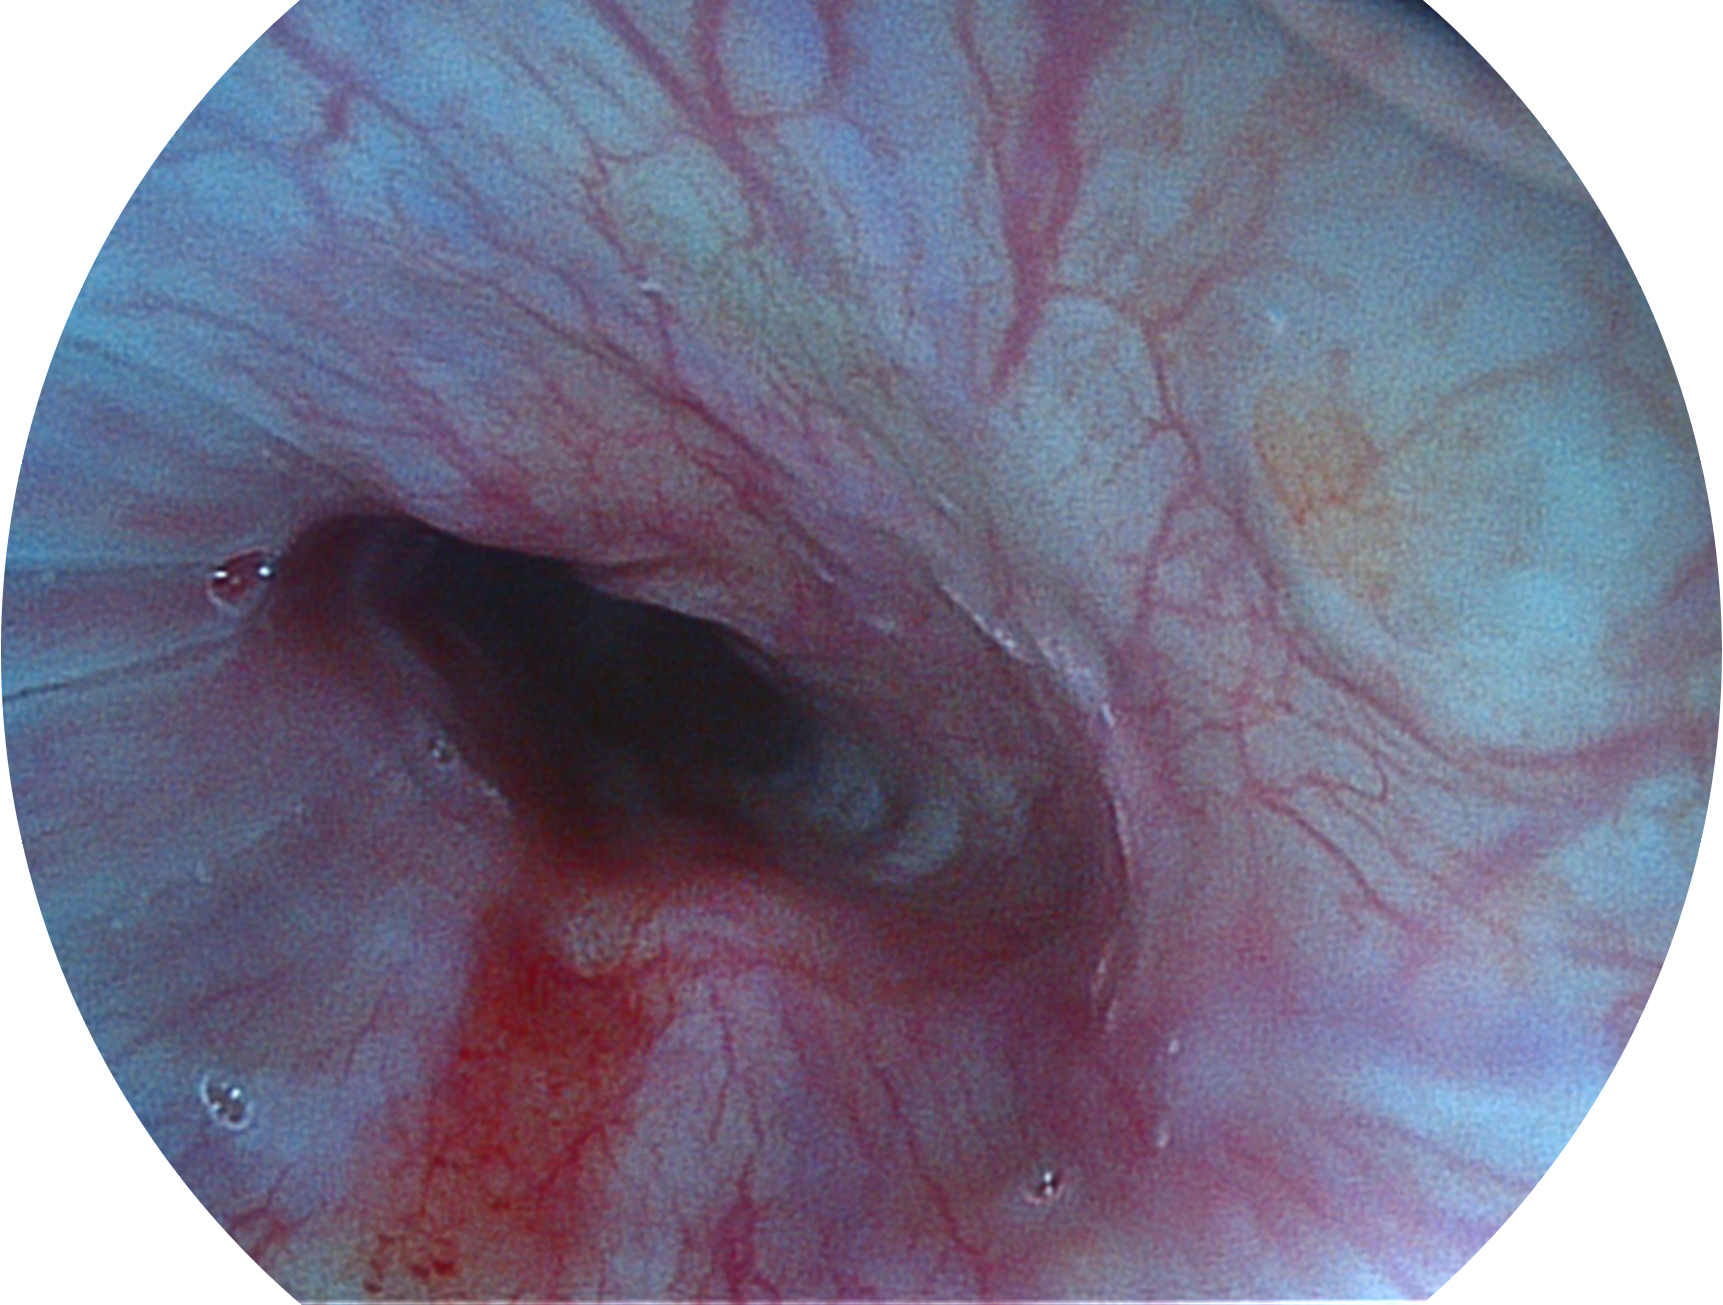

九州酷游新开发的内镜染色技术,主要是基于多波长LED 光源的开发,VLS-55Q 四波长LED 光源是由四个不同颜色的LED光按照相应照明模式所规定的特定发光比例进行合束后形成,合束后形成的照明光的光谱由红光、绿光、蓝光及蓝紫光这四个不同的波段范围构成。具有更高光谱自由度,通过光谱比例的控制,实现了聚谱成像技术,英文全称为“Spectral Focused Imaging, SFI”,缩写为“SFI”和光电复合染色成像技术,英文全称为“Versatile Intelligent Staining Technology, VIST”,缩写为“VIST”。